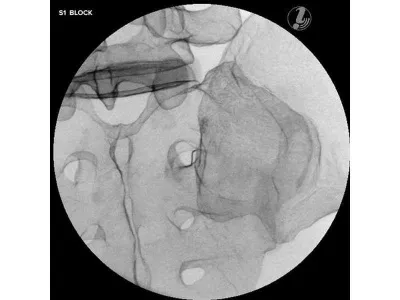

- Блокада позвонка S1